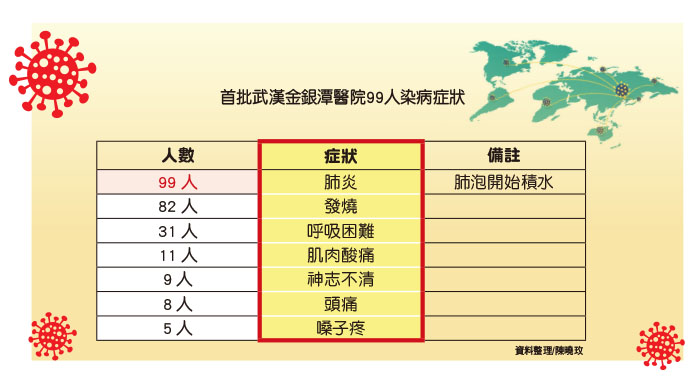

究竟武漢肺炎的病毒如何影響你的身體?一旦染病會對身體產生哪些影響,又會產生哪些症狀?哪些人最脆弱或是死亡?又能怎麼治療呢?我們從第一批武漢金銀潭醫院染病的99人可以看出一些端倪,也可以從他們的身上避免自己身陷危險。

武漢肺炎最先死亡的兩例病人都是男性吸煙者,他們看起來很健康,但是由於長期吸煙削弱肺部功能。其中第一位死亡的病患是一名61歲的男子,他到醫院時已經出現嚴重肺炎、嚴重的呼吸困難,這表示他的肺已經無法為全身的器官供氧。即便醫院讓他使用呼吸機,但他還是出現肺衰竭,心臟也停止了跳動,並在住院後11天死亡。

第二位患者是一名69歲男子,他同樣出現嚴重急性呼吸衰竭症狀,醫院讓他使用葉克膜,但最後仍撒手人寰,死於嚴重肺炎和敗血性休克,而這99名患者中的死亡率至少為10%。由此可知,吸菸嚴重影響肺部的功能,更讓新型冠狀病毒趁虛而入,最終與世隔絕。

截至到1月25日,仍有57人住院,31人已出院,11 人死亡,但這99名患者中仍在住院的還可能會出現死亡,而且曾染病的還可能再度感染。另外,還有許多感染病毒但症狀較輕微的人根本沒有去醫院,而這些人正是防疫的漏洞。

體弱病

一般都認為此次武漢肺炎病毒的傳染源是來自武漢的華南海鮮市場,尤其這首批武漢金銀潭醫院染病的99名病患中有49人跟這個海鮮市場有直接接觸,47人是市場經理或是業主和攤販,還有2人曾到該市場買菜購物,其中受影響最嚴重的是中年男子,他們平均年齡56歲,其中67人為男性。一開始男性患者較多,目前男女患者比例開始接近,但男子略高。

另外值得注意的是,這99名感染者中的大多數人本來就有其他疾病,這就使得他們的免疫系統更脆弱,給病毒可乘之機。40人有心臟問題,包括心臟衰竭和中風,12人有糖尿病。這樣的結果代表最具有風險的是年紀大的人和有病史的人。杜克大學傳染病學教授格利高里・蓋瑞(Gregory Gary)說:「老年人群和已經有病史的人群患病的風險增加,不過,我們還不能確定這增加的風險有多大。但這樣的觀察結果與其他呼吸道病毒是一致的,無論是流感病毒還是冠狀病毒)。有病史的人群,例如接受化療治療的人、孕婦、很小的孩子和年紀大的人是最關注的群體,也是最需要你照顧的。他們本身很難,他們的免疫系統也難以抵抗病毒。」